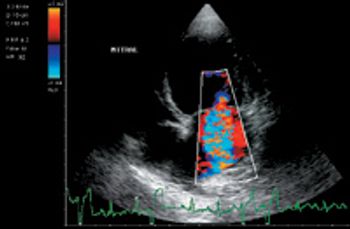

Chronic valve disease (CVD), also called mitral valve disease or endocardiosis, is the most common form of acquired cardiac disease diagnosed in small- and medium-sized dogs. The mitral valve alone is affected in 60 percent of cases of chronic valve disease, whereas only the tricuspid valve is affected in 10 percent of cases. Thirty percent will have both the tricuspid and mitral valves affected. Endocardiosis is an age-related thickening of the mitral valve due to fibroblast proliferation and an increase in collagen and elastic fibers. The thickening of the mitral valve allows a regurgitant volume of blood to be forced from the high-pressure left ventricle into the low-pressure left atrium during systole. Over time, regurgitation can lead to progressive atrial and ventricular enlargement due to volume overload. Severe mitral regurgitation can lead to left-sided congestive heart failure and pulmonary edema formation. Long-term severe mitral regurgitation can lead to generalized heart failure. Right heart..